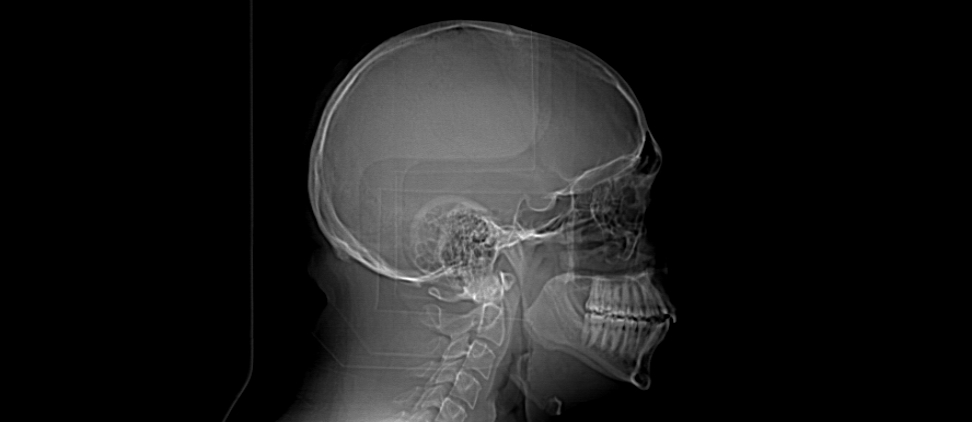

Here are a few shots illustrating how off-kilter my septum is. That line right down the middle is the septum, and it is supposed to be pretty straight. Mine, however, veers off to the left side of my body (the right in the pictures), includes a funky hook-shaped spur, and the whole nasal space is sort of off-kilter and asymmetrical. But it’s nothing that a little modern medicine can’t fix. The last picture has nothing to do with my septum, but I think it’s the coolest image on the my entire C/T scan disk.